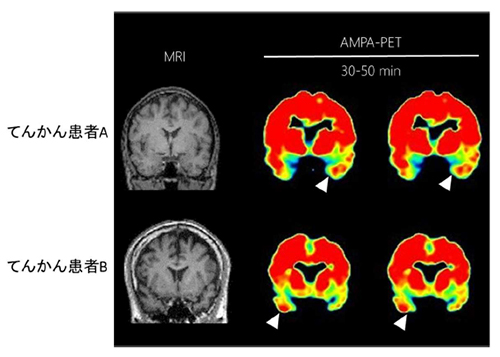

本研究グループは,ヒトの生体脳内で AMPA受容体を可視化する陽電子断層撮像( Positron Emission Tomography:PET)用のトレーサー(化合物: [11C]K-2)を世界で初めて開発した。そして,この物質を動物に用いた前臨床研究と,健常者とてんかん患者に協力いただいた臨床研究により, [11C]K-2が生体内でAMPA受容体を特異的に認識していることを証明した。更に,てんかん患者の病巣(焦点)においてAMPA受容体が多く集積することが観察された。(図2)

図2 てんかん焦点の可視化

てんかん手術を受ける患者の臨床上の病巣(焦点)(白矢印頭の部位)において [11C]K-2の画像値が高くなっている,つまり AMPA受容体が多く集積していることが理解できる。